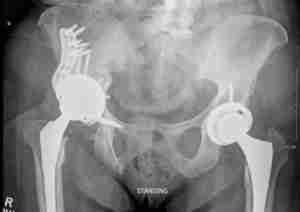

Revision Hip Replacement Surgery

Implant Wear and Loosening

The cause of loosening isn’t always clear. Repetitive high-impact activities, high body weight and wear of the plastic liner between the ball and metal cup could be contributing factors. There is a higher risk for loosening of total hip replacements for patients who undergo a hip replacement at a young age. As the plastic component wears out, the tiny particles are attacked by your body’s immune system. When the immune system attacks healthy bone around your implant, it leads to a condition called “osteolysis”. Loose implants lead to a painful hip replacement.

Recurrent Dislocation

The native hip joint is a ball-and-socket joint. An artificial hip is at a much higher risk for a dislocation than a native hip. Trauma and certain hip positions may cause the ball to escape from the socket. When this happens, your hip is considered dislocated, and can be very painful. Multiple hip dislocations may require you to have a surgery to realign your hip socket. Sometimes you may require a specially designed implant called a “constrained liner” to prevent hip dislocations.

A revision hip replacement may be a salvage operation and often requires more extensive preparation. You will need to have your previous medical charts so that they may be to be reviewed. Dr. Morton will evaluate all your imaging and x-rays. Occasionally he may order more advanced imaging such as a CT or MRI. Laboratory tests will be ordered to determine if your hip is infected or having a reaction to metal components in your hip.